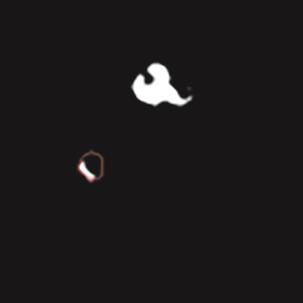

基于逐通道空间自适应选择核卷积与双向边界感知机制的乳腺超声图像病变分割网络

A Breast Ultrasound Images Lesion Segmentation Network Based on Channel-Wise Spatially Adaptive Selective Kernel Convolution and Bidirectional Boundary-Aware Mechanism

乳腺癌是全球女性最常见的恶性肿瘤之一,准确的病变分割对于乳腺癌的早期诊断与治疗具有重要意义。然而,由于病变形态的多样性以及超声成像机制的复杂性,现有基于深度学习的乳腺超声图像病变分割方法在分割准确性方面仍面临巨大挑战。为进一步提升乳腺超声图像中病变区域的分割精度,该文基于经典U-Net架构,提出了一种新型乳腺超声图像病变分割网络(CWSASKM-BBAM-Net)。首先,在网络中引入逐通道空间自适应选择核卷积模块(CWSASKM),根据不同通道的语义特征为每个空间位置自适应选择感受野大小,以增强多尺度信息的建模能力;然后,引入双向边界感知机制(BBAM),通过融合正向与反向注意力,对目标显著区域及其边界进行协同建模,同时逐步提升对非显著区域与病变区域的区分能力,以进一步强化边界信息的表达;最后,在3组公开乳腺超声图像数据集(BUSI、UDIAT和STU)上开展分割实验。结果表明:该方法在数据集BUSI上的杰卡德指数、精确率、召回率和Dice相似系数分别为71.97%、82.85%、81.40%和80.44%,较次优方法分别提升1.69、1.05、1.28和1.84个百分点;在数据集UDIAT上,这4项指标分别达到78.14%、88.31%、86.73%和86.10%,较次优方法分别提升了2.75、2.04、0.56和2.01个百分点;在外部数据集STU上,该方法也取得了优于其他方法的整体表现。实验结果表明,CWSASKM-BBAM-Net在乳腺超声图像分割任务中展现出更优的整体性能。